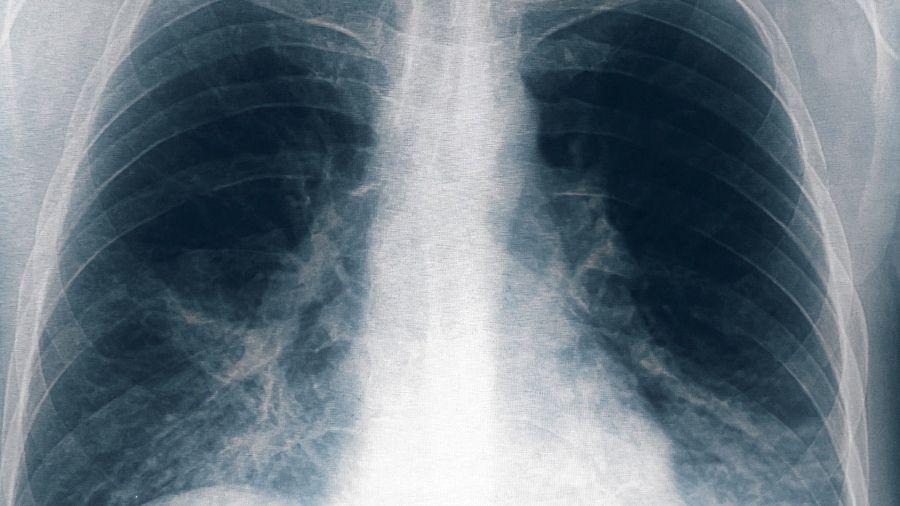

La otra es la ¨enfermedad de los legionarios¨, que se trata de una neumonía muy severa y potencialmente fatal, con un período de incubación de 2 a 10 días y puede cursar con afectación secundaria de otros órganos como riñón, hígado, tracto gastrointestinal y sistema nervioso; es este caso la mortalidad es del 15 a 20%.